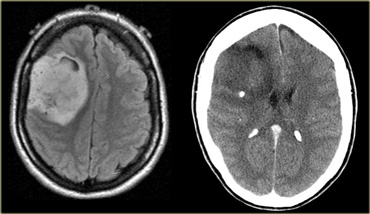

On the left is an image of an intra-axial tumor in an adult.

It is centered in the temporal lobe and involves the cortex.

Although there is massive infiltrative growth involving a large part of the right cerebral hemisphere, there is only minimal mass effect.

There is no enhancement.

These features are typical for a low-grade astrocytoma.